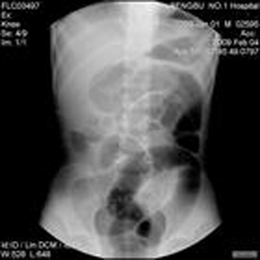

内痔、肛裂常在大便后出血;慢性非特异性结肠炎、结肠憩室、阿米巴痢疾、结肠息肉病等常呈反复、间歇性少量便血;中晚期结肠直肠恶变可为持续性少量便血。急性细菌性痢疾、出血性坏死性结肠炎、肠套叠等便血起病均较急。

成年人便血多是内痔、肛裂、炎性肠病等,内痔出血男性多见,肛裂出血则多见于年轻妇女和便秘患者。儿童便血多为直肠息肉、肠套叠。家族性息肉病多于青春期发病,多为粘液血便。中老年便血则要排除结直肠恶变及结肠憩室的可能。

便血可因小肠病变所致,更多的是乙状结肠、直肠出血。就病变性质来说,肿瘤、炎症、畸形等均可出现便血。血色越鲜红,说明出血部位离肛门越近。

直肠、结肠ai:近年来这几种病明显增多,发病率增加了2-3倍。此病初时可见少量血液覆盖粪便表面,随着病情发展,便血量逐渐增多,也可出现大便变细,甚至发生肠梗阻(不排便、不排气、呕吐、腹部出现包块、腹痛)。粪便可有脓黏液及ai肿组织产生的特殊臭味。当全身出现症状,如食欲下降、消瘦、浮肿、贫血等,已属病变晚期。

溃疡性结肠炎:血色或鲜或暗,几乎每次大便均混有血、脓黏,常有腹痛、腹泻,反复发作或迁延不愈。

大肠息肉:有的属良性,有的易恶变(如腺瘤样息肉、绒毛状腺瘤)发病率随年龄增长而增高,可单个或多个。便血常呈间隙性,血色鲜红,一般血量不多,血液不与粪便混合。粪便本身无特殊变化。